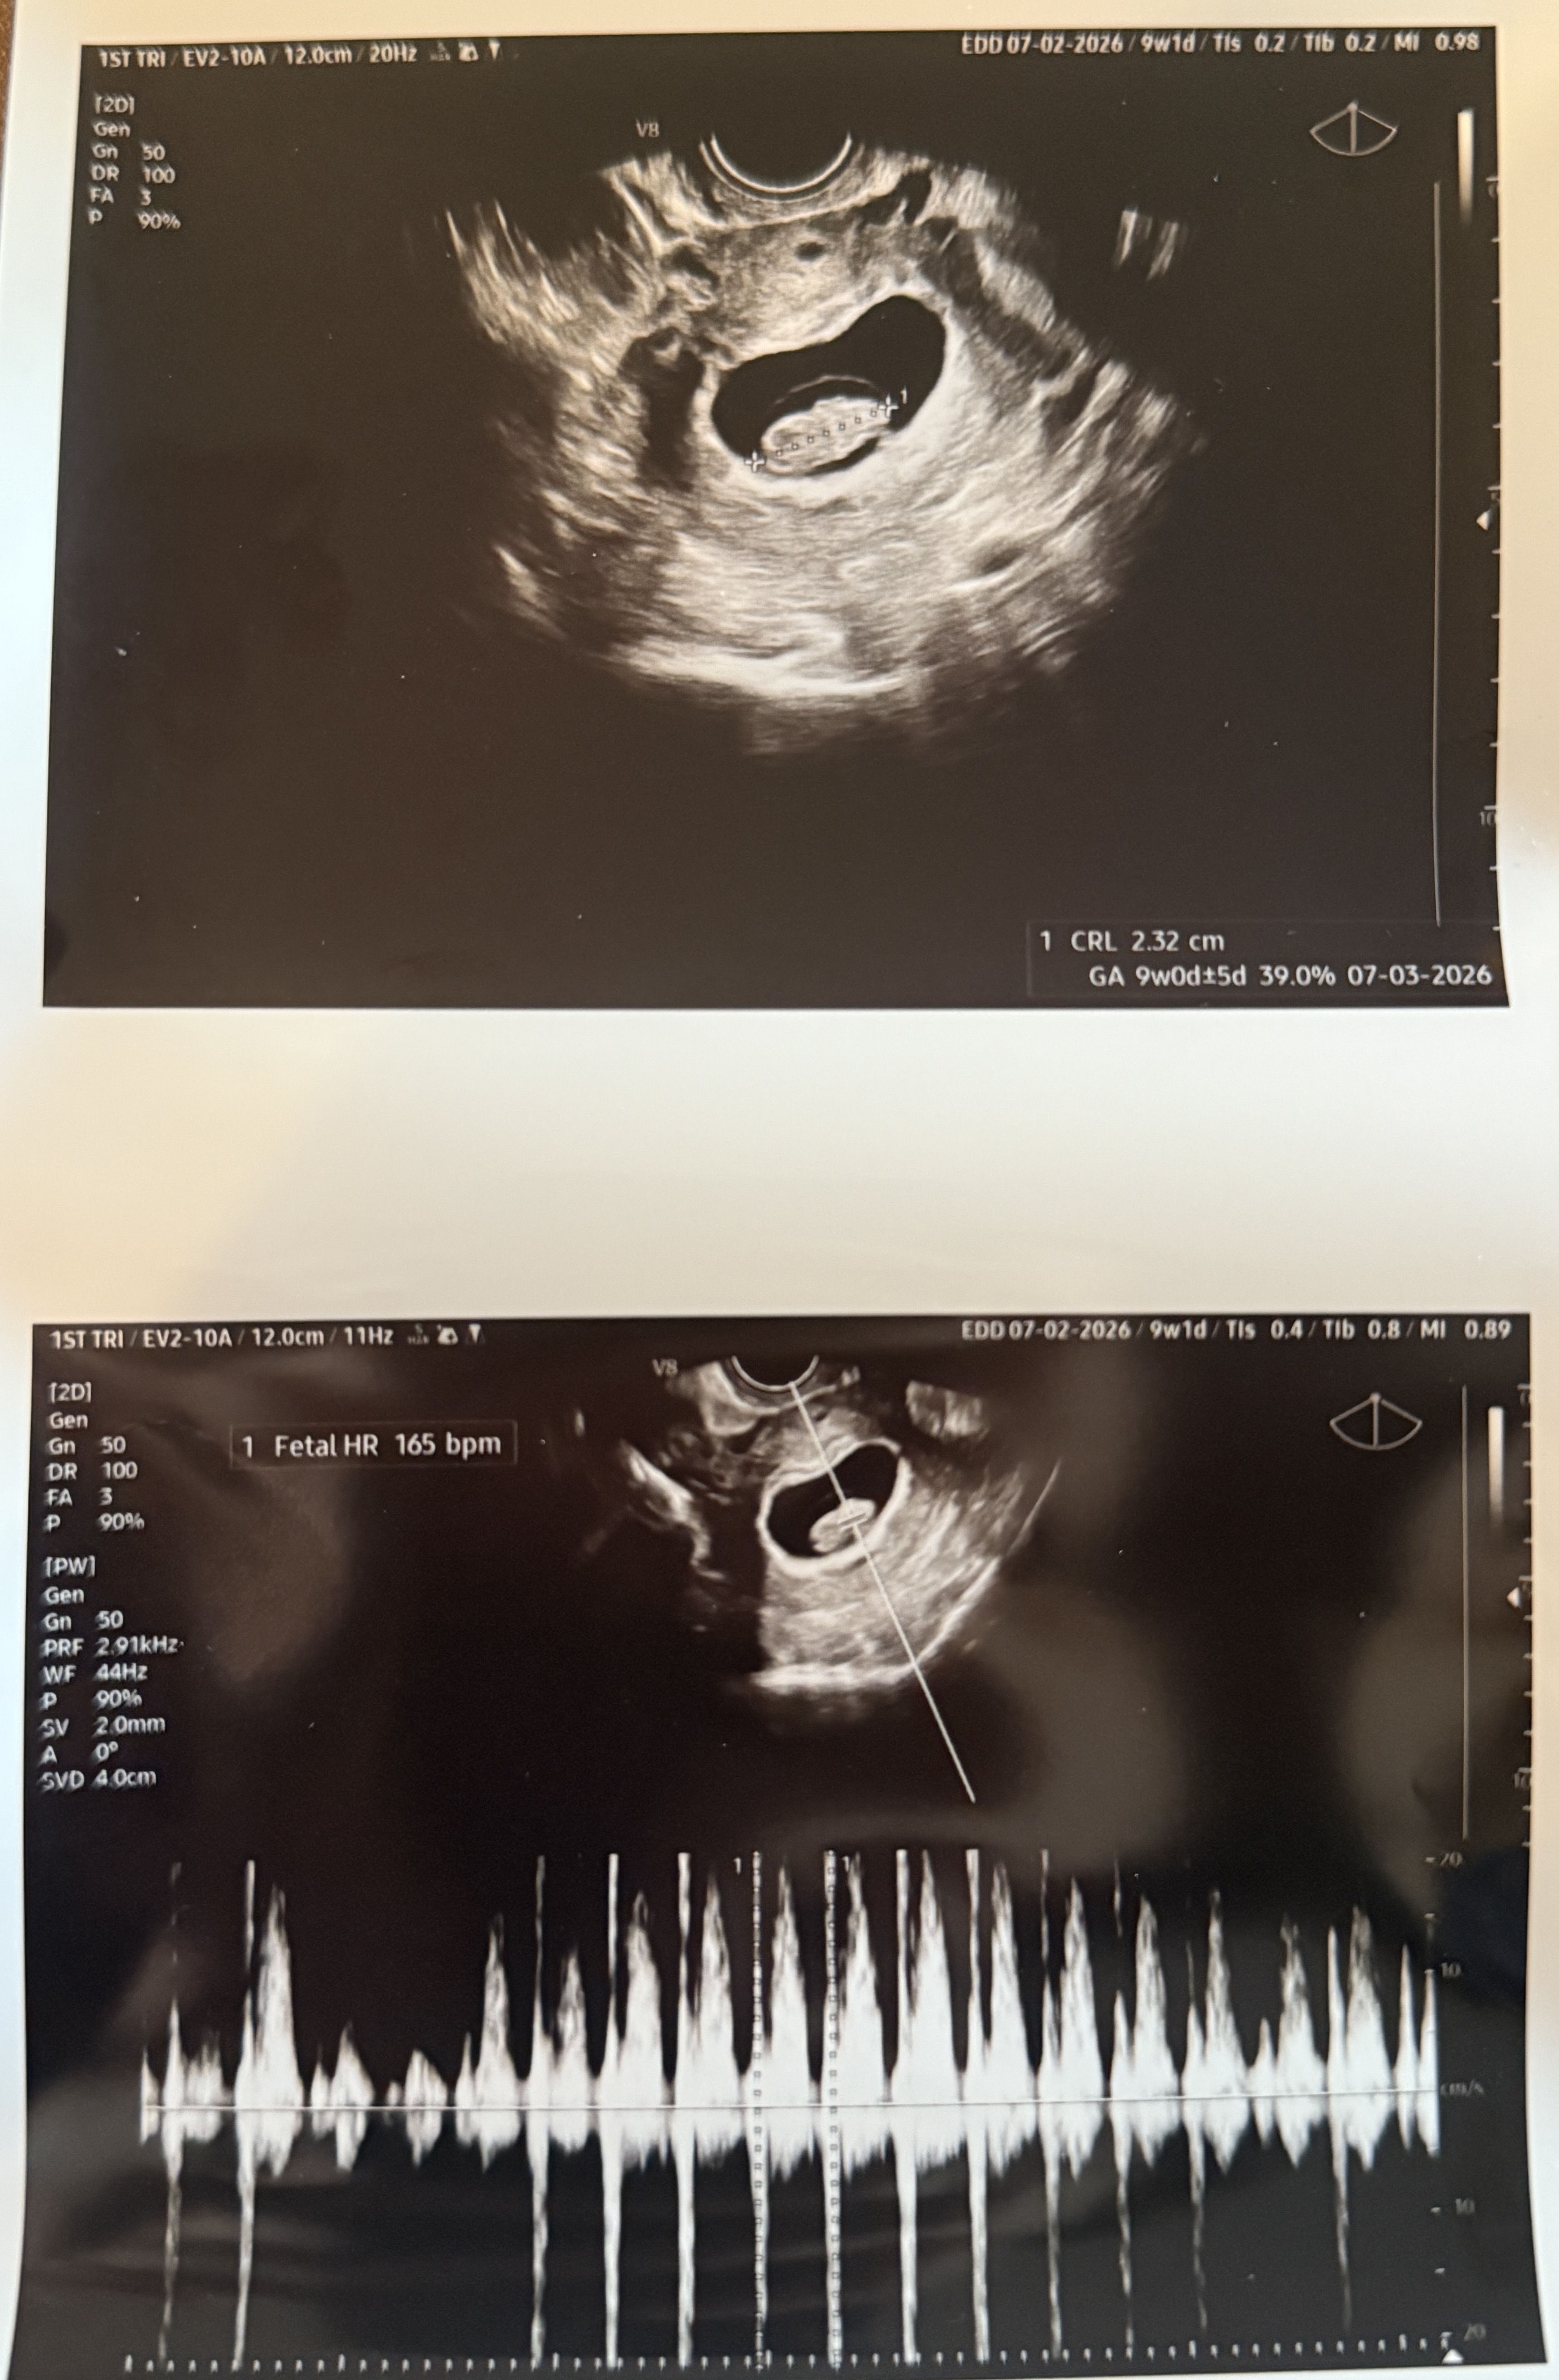

9주 초음파 젤리곰 아닌 땅콩🤣

젤리곰 기대하고 갔는데 땅콩 보고왔어요 ㅋㅋㅋ 저 같은 분 있을까요

저도 9주차때 기대하고 갔는데 땅콩빵 보고 왔어요ㅋㅋ 보는 각도에 따라 다른거 같아요. 원장님께 젤리곰 보고싶은데 다음주에 또 와도 되냐고 여쭤봤더니 병원 왜 돈벌어주냐고 이상있을때만 오라고 그러셔서 젤리곰 못봤어요ㅋㅋ